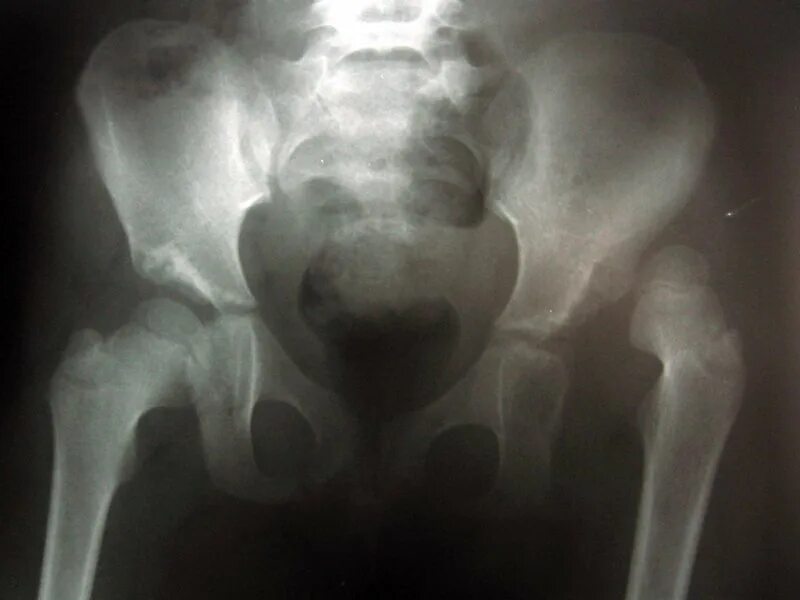

Тазобедренного сустава у детей